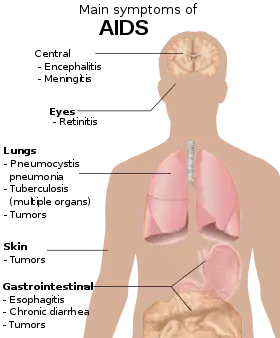

Signs and symptoms

There are three main stages of HIV infection: acute infection, clinical latency, and AIDS.[1][30]

Acquired immunodeficiency syndrome

Acquired immunodeficiency syndrome (AIDS) is defined as an HIV infection with either a CD4+ T cell count below 200 cells per µL or the occurrence of specific diseases associated with HIV infection.[33] In the absence of specific treatment, around half of people infected with HIV develop AIDS within ten years.[33] The most common initial conditions that alert to the presence of AIDS are pneumocystis pneumonia (40%), cachexia in the form of HIV wasting syndrome (20%), and esophageal candidiasis.[33] Other common signs include recurrent respiratory tract infections.[33]

Opportunistic infections may be caused by bacteria, viruses, fungi, and parasites that are normally controlled by the immune system.[40] Which infections occur depends partly on what organisms are common in the person's environment.[33] These infections may affect nearly every organ system.[41]

People with AIDS have an increased risk of developing various viral-induced cancers, including Kaposi's sarcoma, Burkitt's lymphoma, primary central nervous system lymphoma, and cervical cancer.[34] Kaposi's sarcoma is the most common cancer, occurring in 10% to 20% of people with HIV.[42] The second-most common cancer is lymphoma, which is the cause of death of nearly 16% of people with AIDS and is the initial sign of AIDS in 3% to 4%.[42] Both these cancers are associated with human herpesvirus 8 (HHV-8).[42] Cervical cancer occurs more frequently in those with AIDS because of its association with human papillomavirus (HPV).[42] Conjunctival cancer (of the layer that lines the inner part of eyelids and the white part of the eye) is also more common in those with HIV.[43]

Additionally, people with AIDS frequently have systemic symptoms such as prolonged fevers, sweats (particularly at night), swollen lymph nodes, chills, weakness, and unintended weight loss.[44] Diarrhea is another common symptom, present in about 90% of people with AIDS.[45] They can also be affected by diverse psychiatric and neurological symptoms independent of opportunistic infections and cancers.[46]